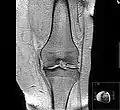

Diagnosis is made with reasonable certainty based on history and clinical examination.[42][43] X-rays may confirm the diagnosis. The typical changes seen on X-ray include: joint space narrowing, subchondral sclerosis (increased bone formation around the joint), subchondral cyst formation, and osteophytes.[44] Plain films may not correlate with the findings on physical examination or with the degree of pain.[45] Usually other imaging techniques are not necessary to clinically diagnose osteoarthritis.

- MRI of osteoarthritis in the knee, with characteristic narrowing of the joint space.